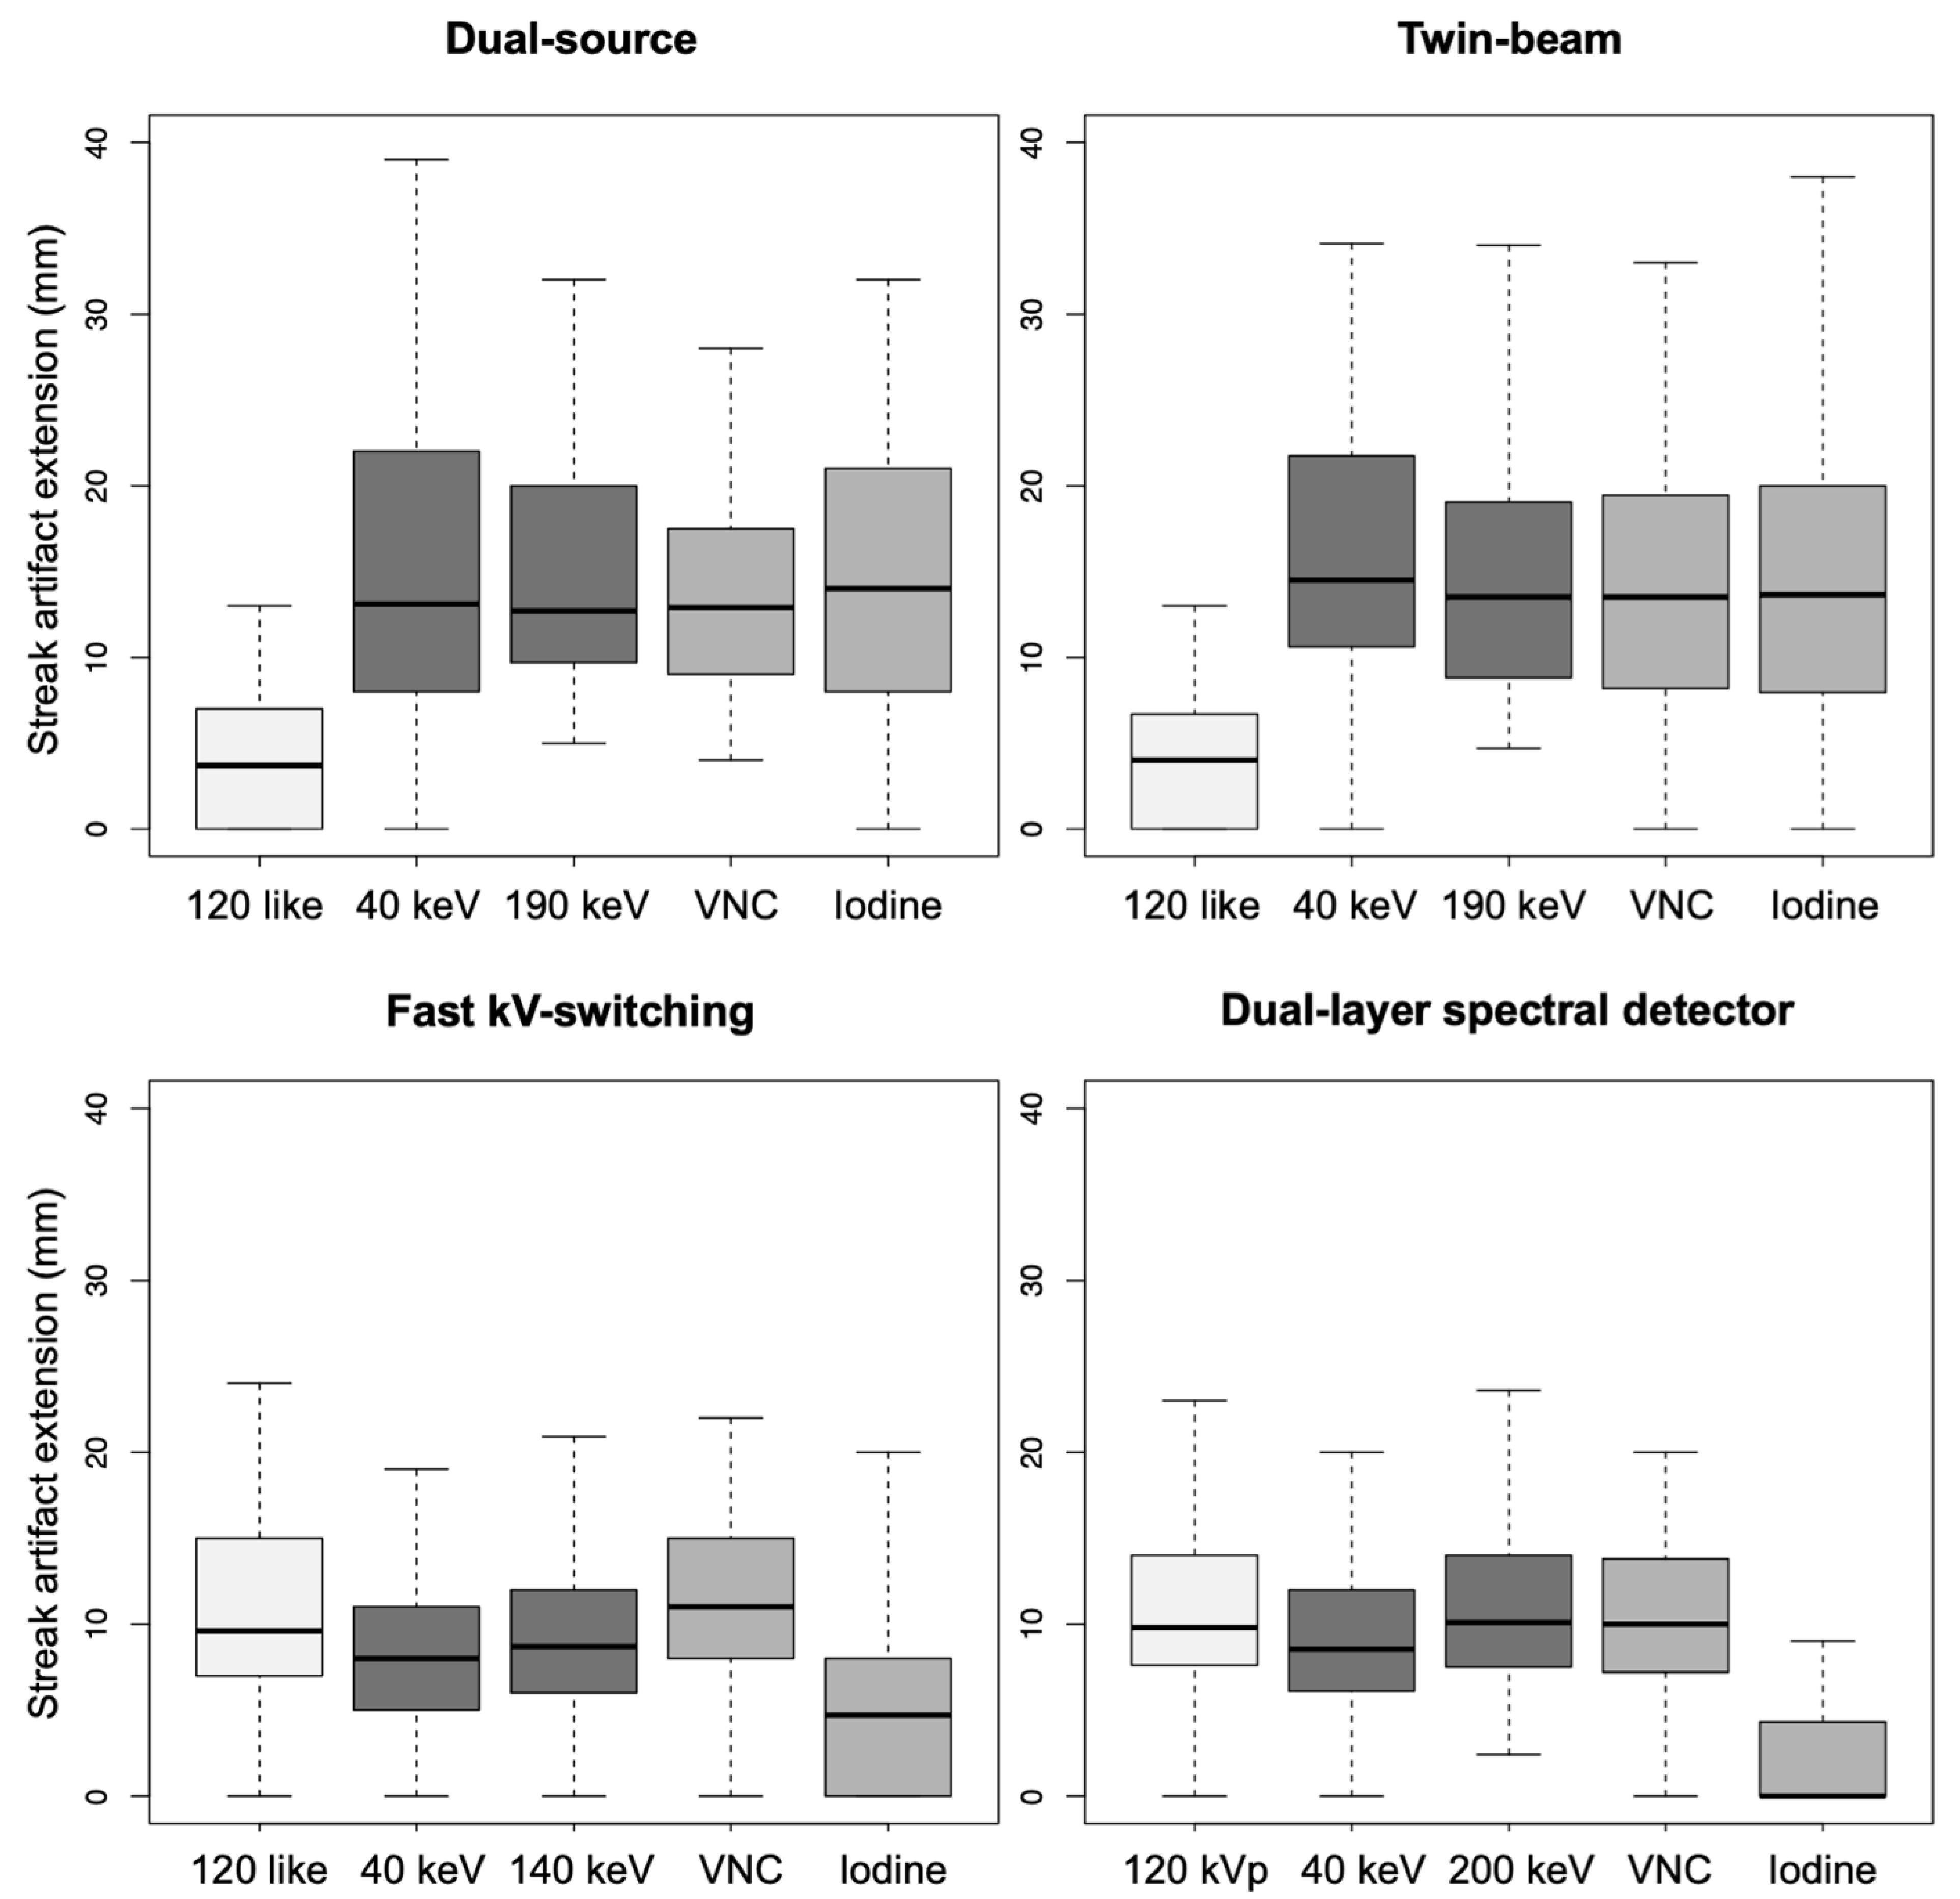

- Dual-source scanner: Depth of extension of visceral-motion-related artifacts into the liver (see Figure 2 and Figure 3) was significantly shorter (p < 0.001, each) for 120-kVp-like images (mean length: 5 ± 6 mm) compared with 40-keV (mean length: 16 ± 11 mm), 190-keV (mean length: 16 ± 9 mm), VNC (mean length: 15 ± 10 mm), and iodine (mean length: 16 ± 11 mm) images. Mean ROI measurements (HU or iodine concentration, respectively) were significantly different in the bright and dark artifact components compared to the neighboring liver parenchyma not affected by artifacts in 40-keV (p < 0.001, each), 190-keV (p < 0.001, each), VNC (p < 0.001, each), and iodine images (p < 0.001, each). However, in 120-kVp-like images, mean ROI measurements were not significantly different in bright (ROImin) artifact components compared to unaffected liver parenchyma (p = 0.32), as opposed to dark (ROImax) artifact components (p < 0.001).

- Twin-beam scanner: Depth of extension of visceral-motion-related artifacts into the liver was significantly shorter (p < 0.001, each) for 120-kVp-like images (mean length: 4 ± 5 mm) compared with 40-keV (mean length: 18 ± 12 mm), 190-keV (mean length: 16 ± 11 mm), VNC (mean length: 15 ± 11 mm), and iodine (mean length: 16 ± 11 mm) images. Mean ROI measurements were significantly different in the bright and dark artifact components compared to unaffected liver parenchyma in 120-kVp-like (p = 0.006, p = 0.03), 40-keV (p < 0.001, each), 190-keV (p < 0.001, each), VNC (p < 0.001, each), and iodine images (p < 0.001, each).

- Fast kV-switching scanner: Depth of extension of visceral-motion-related artifacts into the liver was significantly shorter (p < 0.001, each) for iodine (mean length: 6 ± 7 mm) images compared with 120-kVp-like (mean length: 11 ± 7 mm), 40-keV (mean length: 9 ± 8 mm), 140-keV (mean length: 10 ± 8 mm), and VNC (mean length: 13 ± 8 mm) images. Mean ROI measurements were significantly different in the bright and dark artifact components compared to unaffected liver parenchyma in 120-kVp-like (p < 0.001, each), 40-keV (p < 0.001, each), 140-keV (p < 0.001, each), VNC (p < 0.001, each), and iodine images (p < 0.001, each).

- Dual-layer spectral detector scanner: Depth of extension of visceral-motion-related artifacts into the liver was significantly shorter (p < 0.001, each) for iodine (mean length: 2 ± 5 mm) images compared with 120-kVp (mean length: 11 ± 5 mm), 40-keV (mean length: 10 ± 6 mm), 200-keV (mean length: 11 ± 5 mm), and VNC (mean length: 11 ± 5 mm) images. Mean ROI measurements were significantly different in the bright and dark artifact components compared to unaffected liver parenchyma in 120-kVp (p < 0.001, each), 40-keV (p < 0.001, each), 200-keV (p < 0.001, each), and VNC (p < 0.001, each) images. However, in iodine images mean ROI measurements were not significantly different in bright (ROImax) artifact components compared to unaffected liver parenchyma (p = 0.15), as opposed to dark (ROImin) artifact components (p < 0.001). Further details on quantitative artifact measurements are provided in Table 2 and the Supplementary Material.